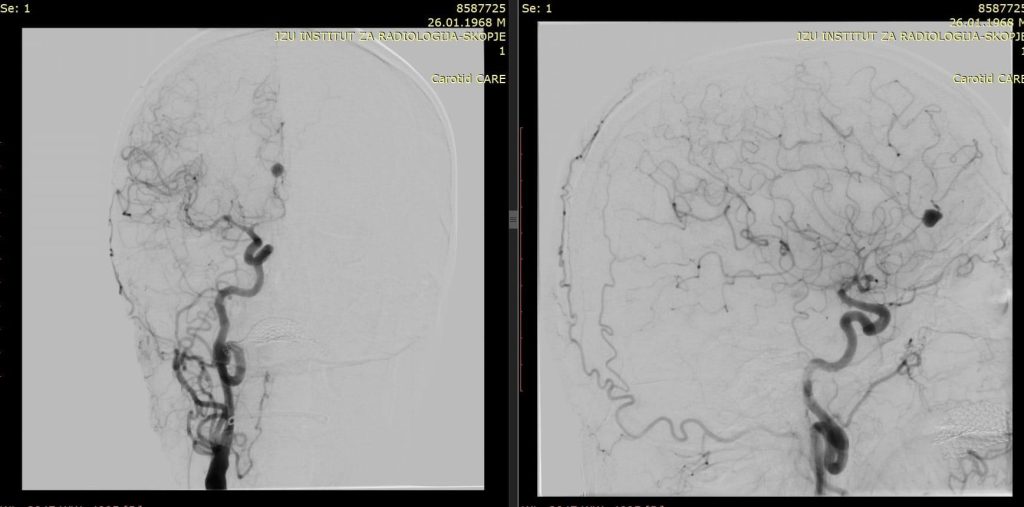

На Универзитетска клиника за неврохирургија беше извршена комплексна микрохируршка интервенција кај 57-годишен пациент со руптурирана аневризма на мозочен крвен сад.

Оваа иновативна метода претставува напредна техника која овозможува визуелизација на крвниот проток во реално време за време на операцијата.

– Со примена на контрастно средство, хирурзите можат прецизно да ја проценат проодноста на крвните садови и да го потврдат целосното исклучување на аневризмата, што е клучно за успешен исход, појаснува д-р Благој Шунтов, специјалист по неврохирургија и раководител на тимот.